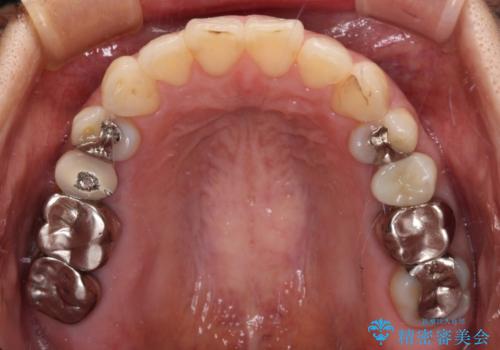

矯正治療後には、左下奥歯の症状がないことを確認し、セラミッククラウンにて補綴治療を行うこととしました。

矯正治療後のレントゲン写真では、根尖部に認められた病変(骨の溶けていた像)は消失していることが分かりました。